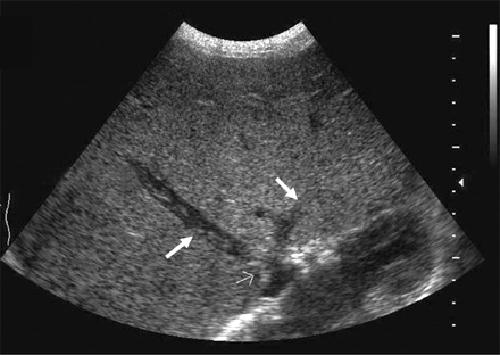

What is the sonographic appearance of Portal venous hypertension?

Portal vein measures greater than 13mm

Collateral

circulation

Flow reversal

Ascites

Hepatosplenomegaly